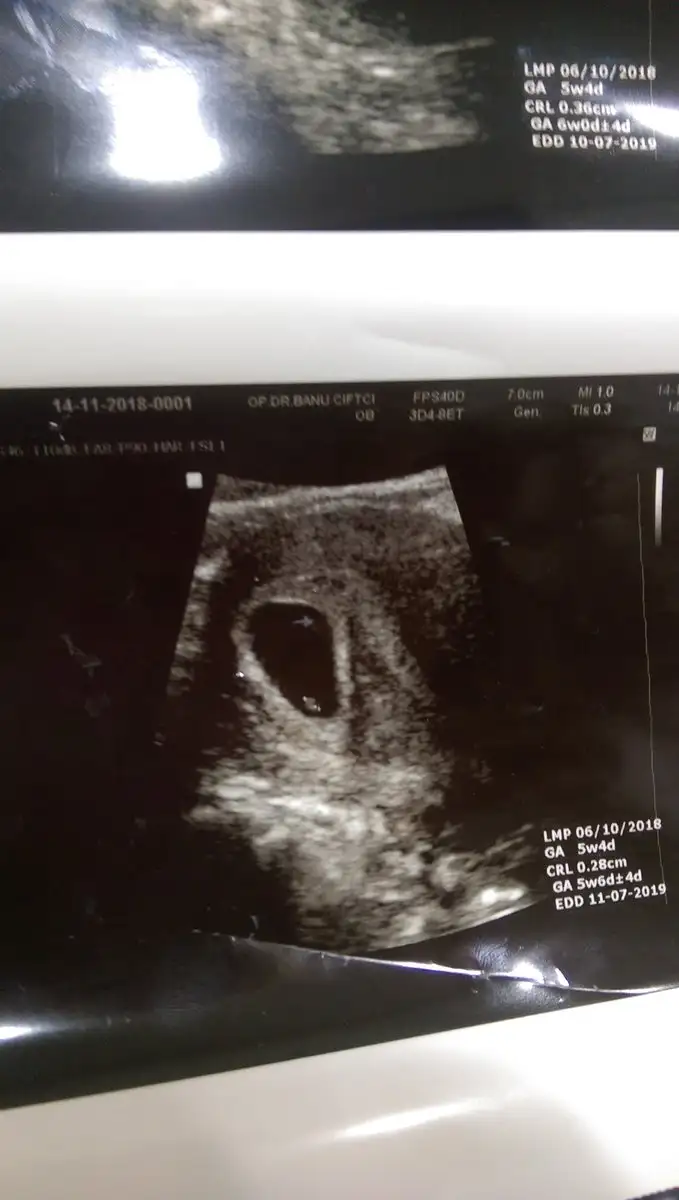

Hosgeldin canim hayirli ugurlu olsun insallah minnakinHayırlı sabahlar hayırlı kandiller hanımlar ben de yeniyim. Rabbimden bi aksilik olmazsa temmuz annesi olacağm:)

Kalp atışını duyduk çok şükür sata uyumlu![]()